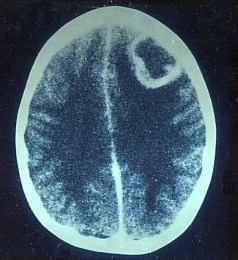

On examination she has a temperature of 39°C, has neck stiffness and is drowsy.

What is the most likely diagnosis?

The patient’s symptoms are important here in establishing the diagnosis as she has a temperature and signs of meningeal irritation suggesting infection.

The CT head scan shows a frontal space occupying lesion with rim enhancement suggesting tumour/metastasis or abscess.

Thus with her presentation the likely diagnosis is abscess.